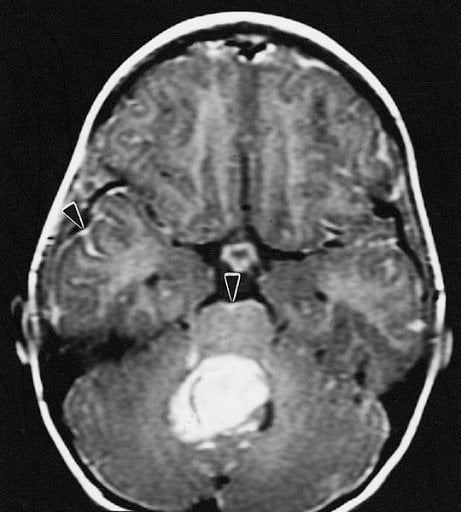

Medulloblastoma is the most common malignant brain tumor, affecting about 500 children under the age of 10 in the United States annually. Current treatment options for medulloblastoma include aggressive surgery, radiation, and chemotherapy. Today, over two-thirds of children are successfully treated. However, survivors generally suffer long-term side effects such as cognitive and developmental disabilities due to the aggressive treatment, and in many cases the tumor reappears within two years after treatment.

Image Source: The medulloblastoma MRI scan image is credited to The Armed Forces Institute of Pathology and is in the public domain.